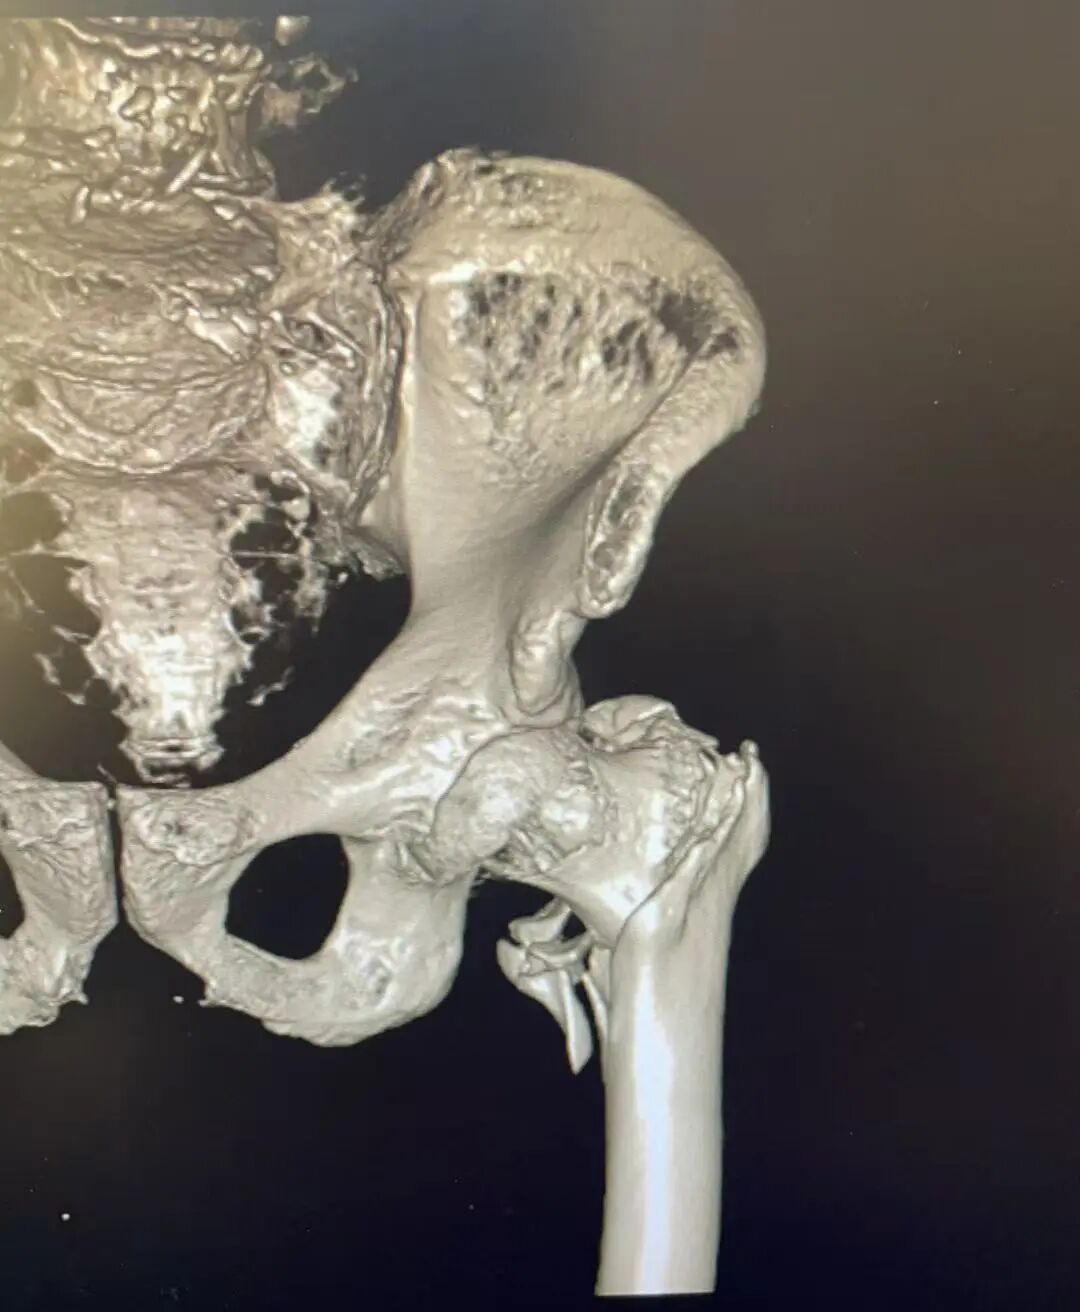

患者术前影像

入院后,急诊科迅速为陈大爷 开通绿色通道 ,第一时间完善各项检查。CT结果显示:左侧股骨大粗隆粉碎性骨折,伴局部碎裂骨片分离错位。考虑到陈大爷 年事已高,且基础疾病较多, 骨科团队迅速行动,组织内科、麻醉科等 多学科专家进行会诊评估讨论 。经过全面、细致的分析,最终确定 闭合复位PFNA内固定术为首选治疗方案 。